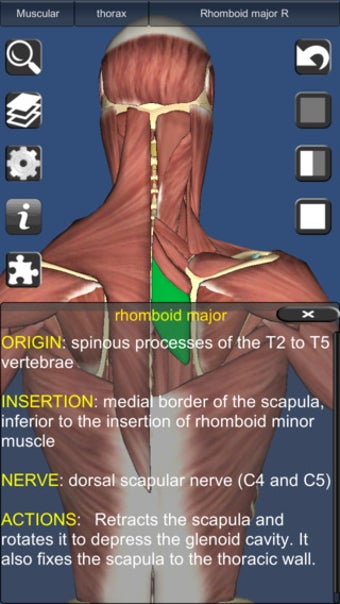

يشبه 3D Anatomy Lite سلسلة Essential Anatomy من التطبيقات من حيث أنه يوفر ميزة ممتازة أداة ثلاثية الأبعاد للمعلمين والطلاب وعشاق الطب العام من أجل استكشاف جسم الإنسان strong>.

على الرغم من أنها لا تبدو رائعة مثل Essential Anatomy ، إلا أنها مفصلة مع القدرة على اعرض النص من أي زاوية strong> بالرغم من أنه يتعين عليك الترقية إلى الإصدار الكامل لمشاهدة كل شيء. p> هناك أيضًا اختبارات ثلاثية الأبعاد strong> لاختبار تكوين معرفتك 3D Anatomy Lite مصدر ممتاز للطلاب. p>